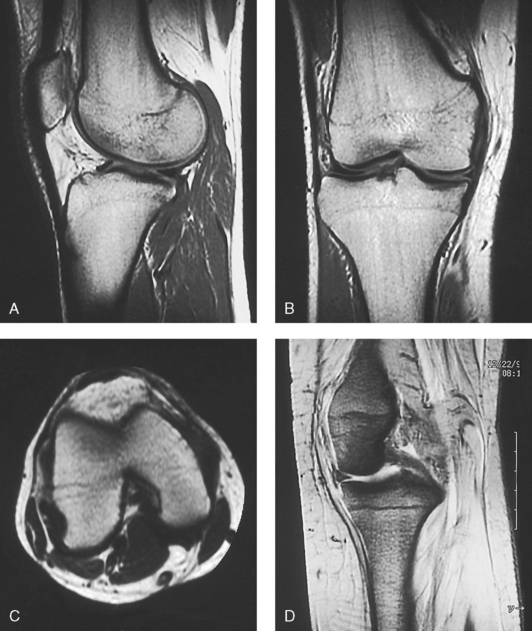

Secondary ossification occurs after birth when a separate bone begins to develop at both ends of each long bone. Each end is called the epiphysis (Fig. 3-15, B). At first, the diaphysis and epiphysis are distinctly separate. As growth occurs, a plate of cartilage called the epiphyseal plate develops between the two areas (Fig. 3-15, C). This plate is seen on long bone radiographs of all pediatric patients (Fig. 3-16, A). The epiphyseal plate is important radiographically because it is a common site of fractures in pediatric patients. Near age 21 years, full ossification occurs, and the two areas become completely joined; only a moderately visible epiphyseal line appears on the bone (Fig. 3-16, B).

Fig. 3-16 A, Radiograph of a 6-year-old child. Epiphysis and epiphyseal plate shown on knee radiograph (arrows). B, Radiograph of same area in a 21-year-old adult. Full ossification has occurred, and only subtle epiphyseal lines are seen (arrows). C, PA radiograph of hand of a 2½-year-old child. Note early stages of ossification in epiphyses at proximal ends of phalanges and first metacarpal, distal ends of other metacarpals, and radius. (C, From Standring S: Gray’s anatomy, ed 40, New York, 2009, Churchill Livingstone.) Churchill Livingstone